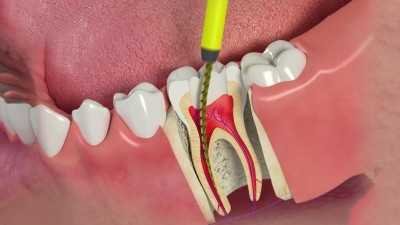

Việc cho Arsenic vào ống tuỷ khi nội nha là một việc làm nguy hiểm. Vì nếu để Arsenic rò rĩ ra ngoài thì việc gây nên hoại tử nha chu và xương là chuyện thường gặp .

Bên cạnh đấy nếu để Arsenic vào ống tuỷ có nguy cơ gây nên các trường hợp viêm quanh chóp sau đó, đặc biệt nguy hiểm với các ống tuỷ lớn và có lỗ chóp mở rộng.